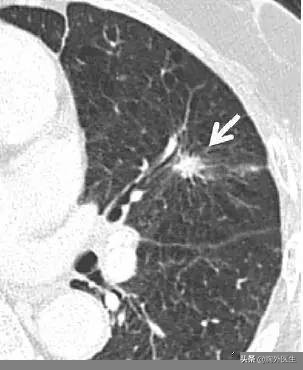

1、从CT上来讲,恶性的肺结节有这些特征:呈分叶状或不规则的形状、边缘有毛刺、周围胸膜凹陷。这些都是由于肺癌向各个方向的生长速度不均匀所引起的。这些表现在肺部良性肿瘤里面一般不出现,可以作为影像学诊断的依据。但是,CT检查由于是通过射线等手段去了解肺结节,只能给出倾向性的一个判断,有一定的误差。要想100%确定良恶性只有取活检行病理切片。这就像警察抓小偷一样,先通过监控等技术手段大规模的排查,找到可疑的嫌疑人(相当于CT),但找到嫌疑人并不能定罪,从理论上来讲仍有抓错的可能,只有通过最后的审问才能确定是否有罪(相当于病理切片)。

形态不规则,有分叶、毛刺、胸膜凹陷